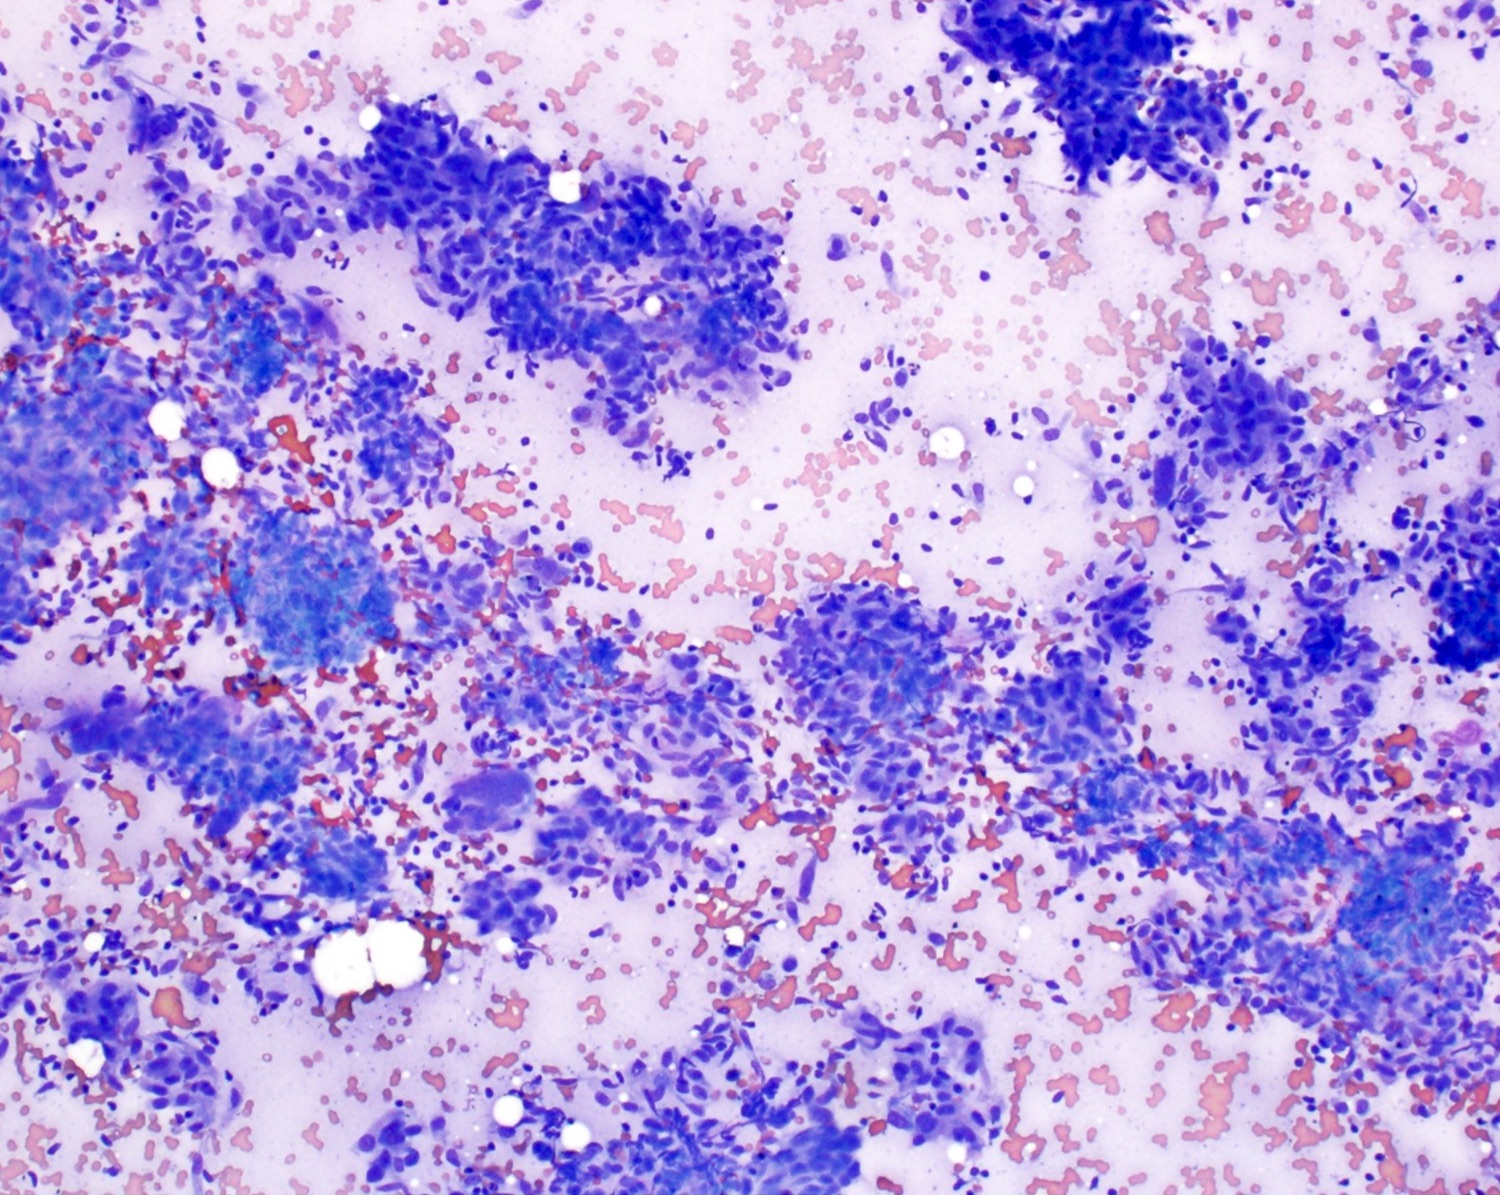

Cytology description

- Well differentiated tumors have elongated cells, isolated cells, tightly cohesive clusters or syncytia (Cibas: Cytology - Diagnostic Principles and Clinical Correlates, 4th Edition, 2014)

- Poorly differentiated: large spindle shaped or epithelioid shaped pleomorphic nuclei (Cibas: Cytology - Diagnostic Principles and Clinical Correlates, 4th Edition, 2014)

- Rhabdoid forms may occur in some epithelioid angiosarcomas (Cibas: Cytology - Diagnostic Principles and Clinical Correlates, 4th Edition, 2014)

- Discohesive epithelioid cells with nuclear pleomorphism and occasional spindle cells (Cibas: Cytology - Diagnostic Principles and Clinical Correlates, 4th Edition, 2014)

- Variably cellular with necrotic background (Cancer Cytopathol 2016;124:659)

- Dense cytoplasm with cytoplasmic vacuoles containing red blood cells (erythrophagocytosis) or neutrophils (Cancer Cytopathol 2016;124:659)

- Endothelial wrapping suggestive of vascular channel formation (Cancer Cytopathol 2016;124:659)

- Large, atypical round to oval nuclei with prominent bar shaped nucleoli (Cancer Cytopathol 2016;124:659)

- Multinucleated tumor giant cells with atypical mitotic figures (Cancer Cytopathol 2016;124:659)

Cytology images